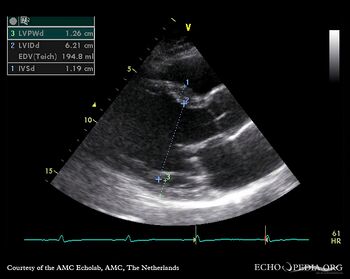

| Prolaps of PMVL

M-Mode through left ventricle, dilated LV